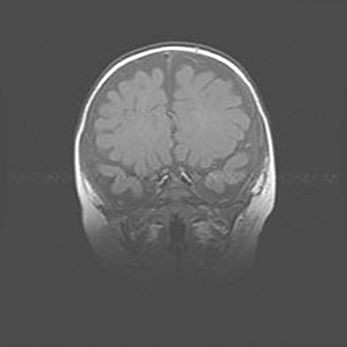

Церебральная ишемия II.

Возраст: 5 дней

Вес: 3400 г

Пол: женский

Окружность головы: 35 см

Срок гестации: 39 недель

Церебральная ишемия – это заболевание, характеризующееся недостаточностью (гипоксией) либо полным прекращением (аноксией) снабжения мозга кислородом по причине закупорки одного или нескольких сосудов. Это приводит к  что метаболическим расстройствам различной степени тяжести в тканях головного мозга, развитию коагуляционных некрозов и гибели нейронов.